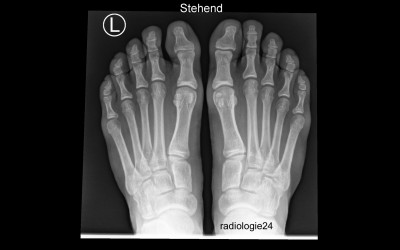

Radiologie-Quiz

Röntgenfall des Monats

Geben Sie Ihre Diagnose ab!

mehr >>